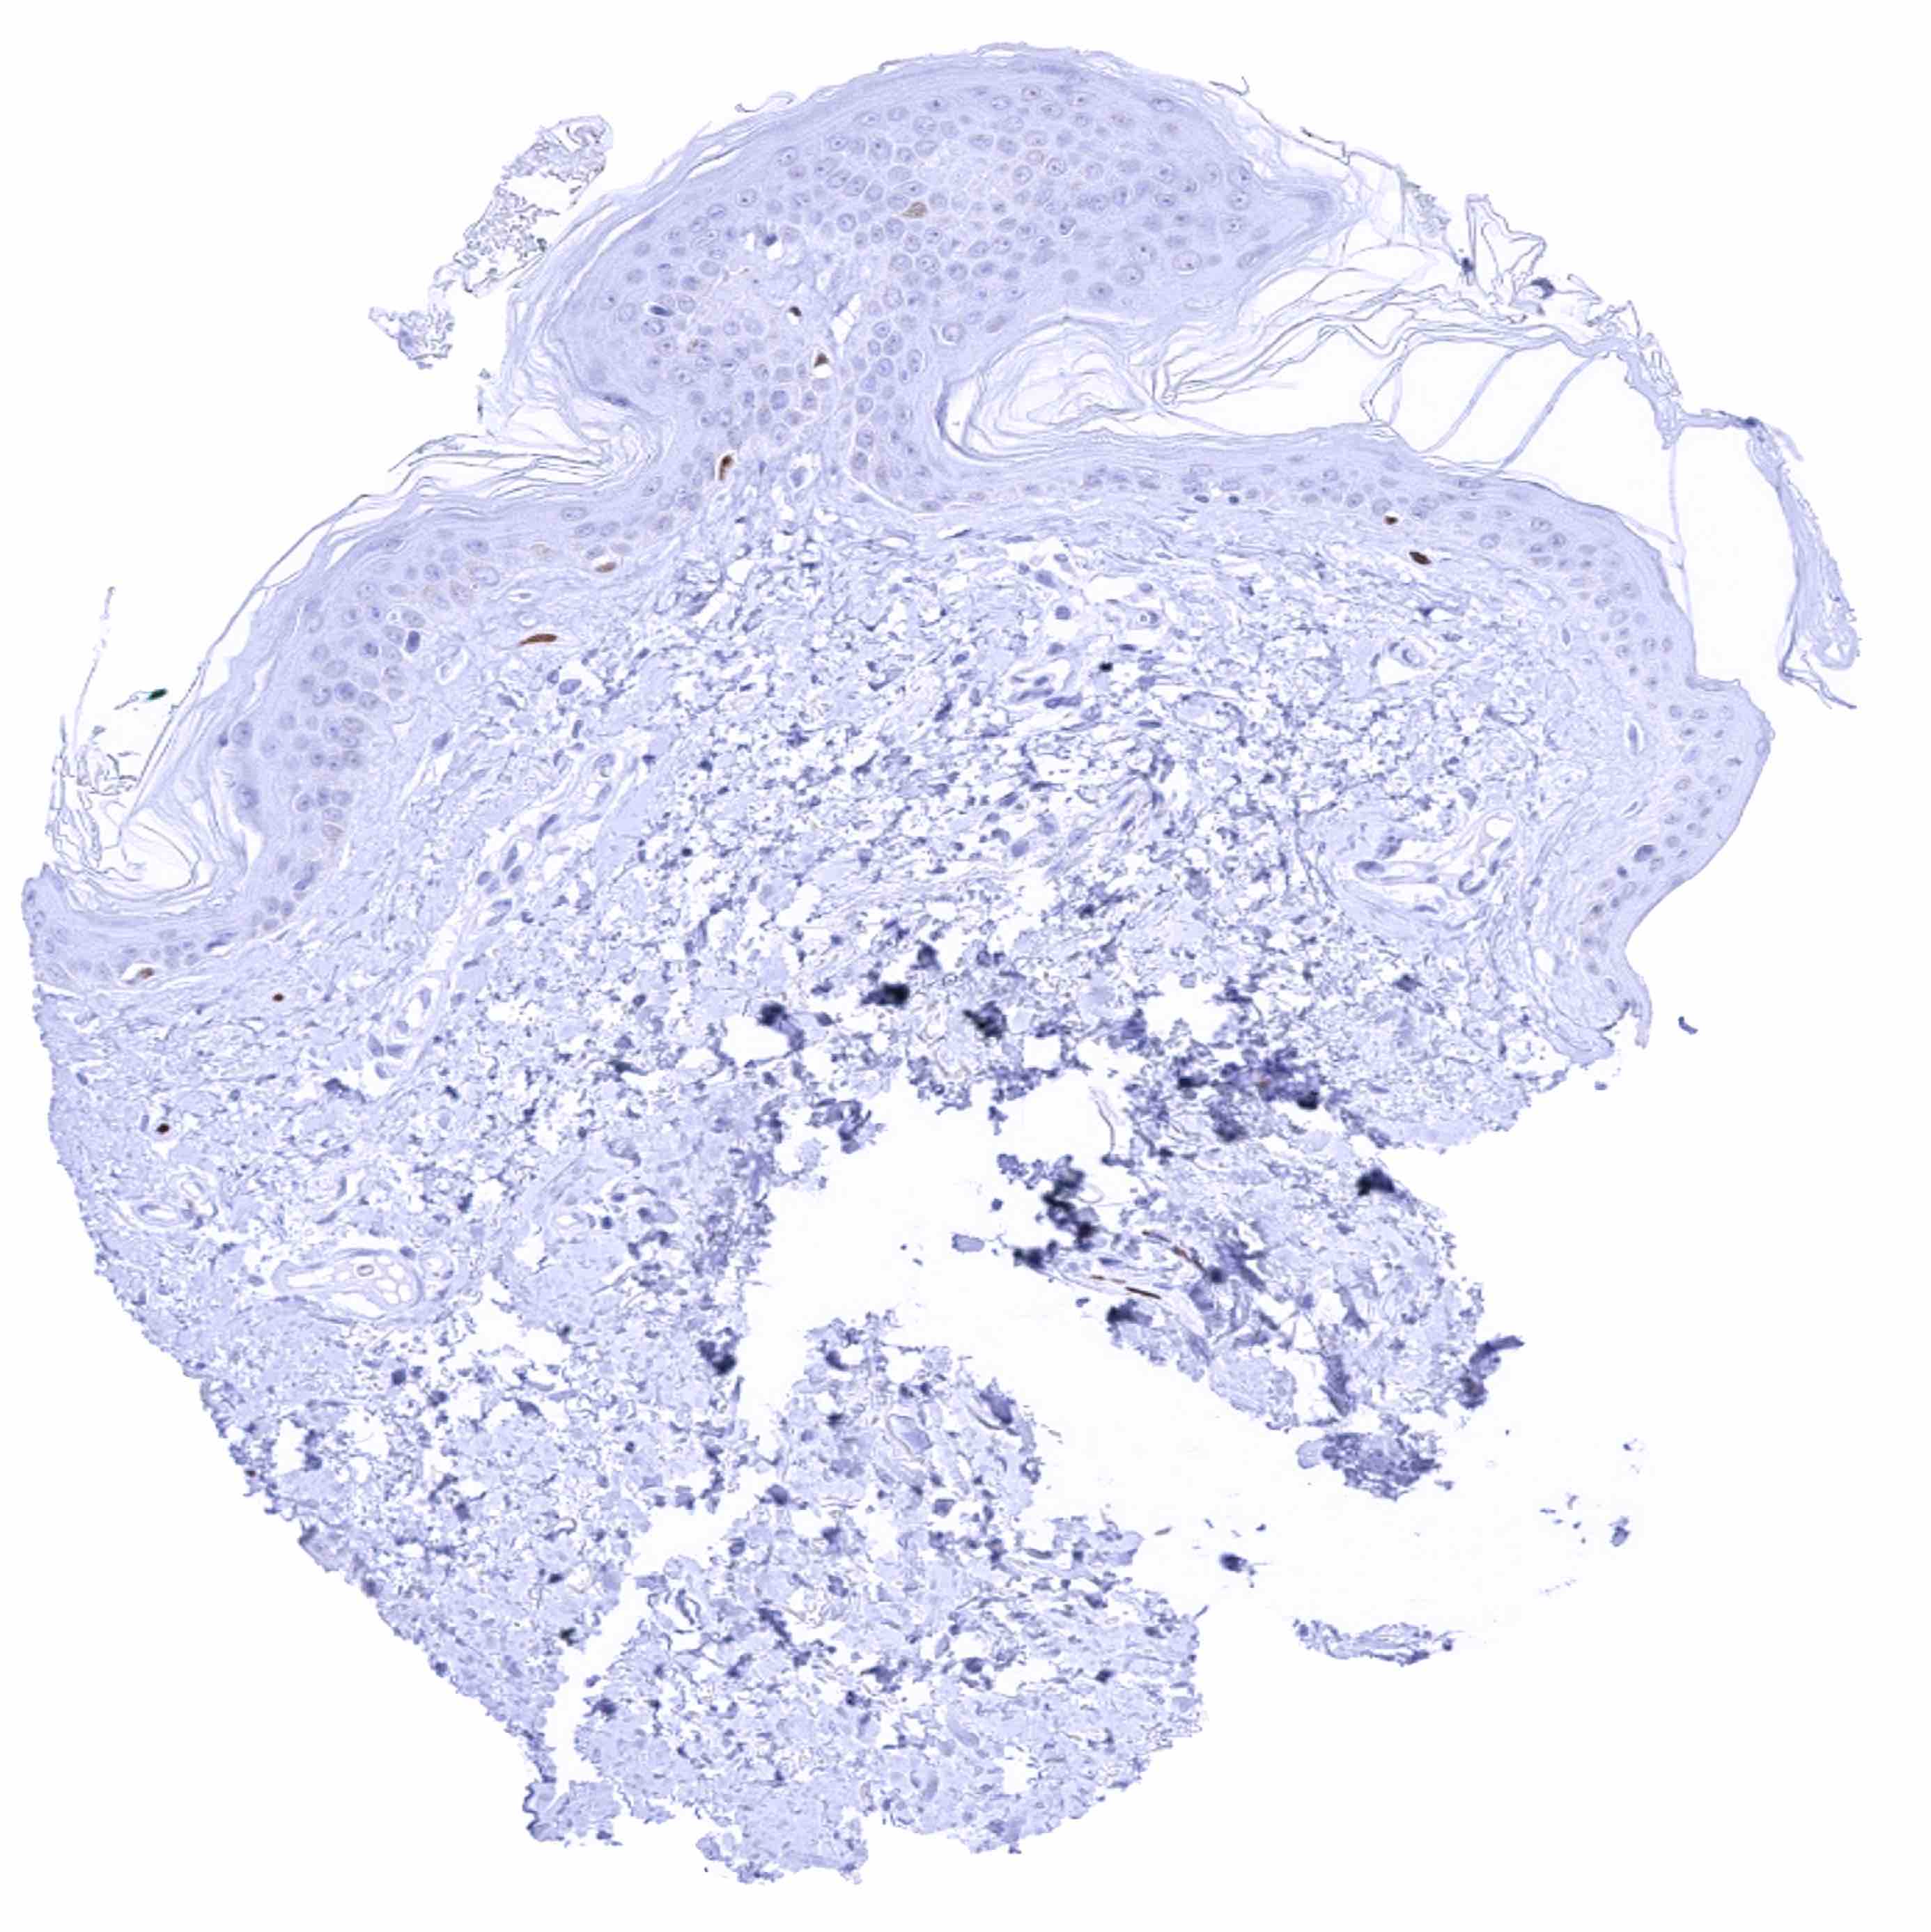

Skin – Strong SOX2 positivity few epidermis-adjacent spindle shaped (neural_) cells in the dermis

Skin, hairfollicel and sebaceous glands – Strong SOX2 positivity few hair follicle-adjacent spindle shaped (neural_) cells in the dermis